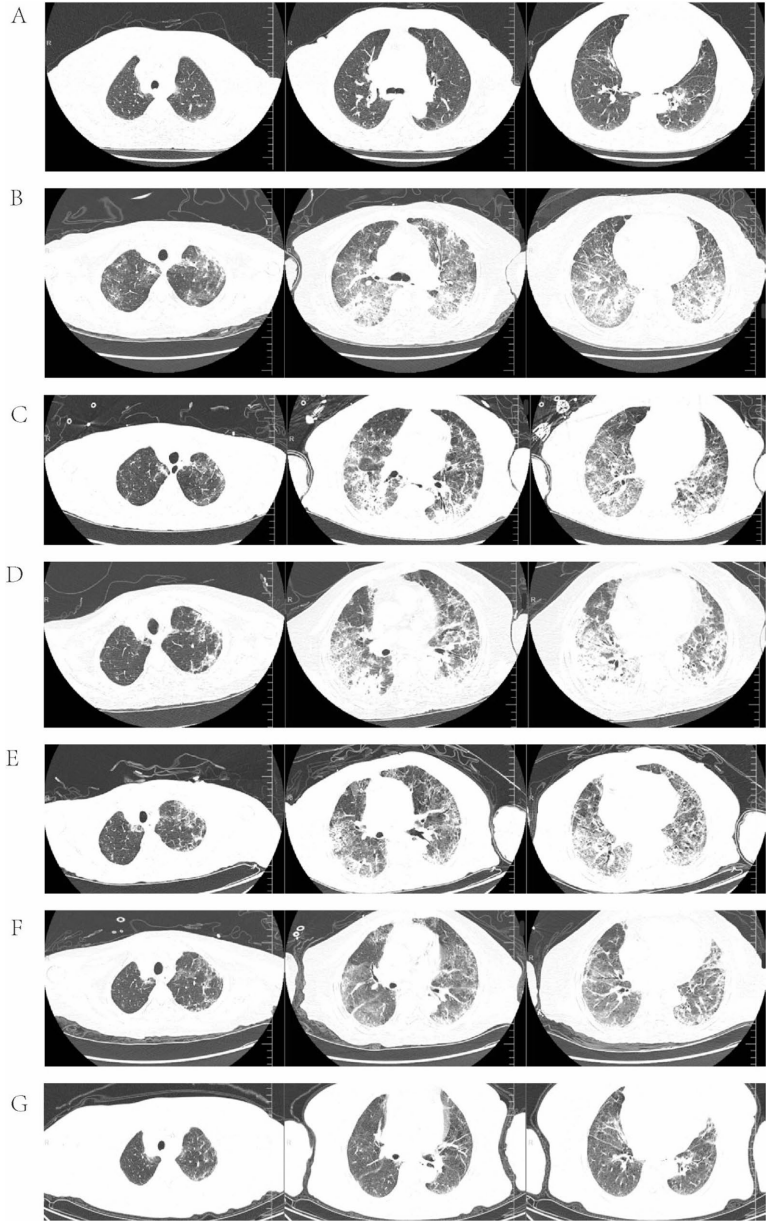

通过病理切片和免疫组化染色(

),确诊患者为HER2(3+)阳性UTUC伴多发转移。基线CT显示肺部正常(

),但联合用药两次后即出现典型ILD影像学改变(

)。